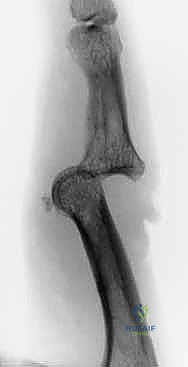

3. إدخال السلك المحوري (Axis Pin) - الخطوة الأهم

هذه هي الخطوة الأكثر حرجاً في العملية. يجب على الجراح تحديد مركز دوران مفصل PIP بدقة متناهية (Center of Rotation). يتم إدخال سلك معدني دقيق (K-wire) عبر رأس السلامية الدانية تماماً في مركز اللقمتين. إذا تم وضع هذا السلك بشكل خاطئ ولو بمليمترات، فإن المفصل سيتعرض للشد غير المتكافئ أثناء الحركة مما يؤدي إلى فشل العملية. يستخدم الدكتور هطيف جهاز الأشعة المرئية (Fluoroscopy - C-arm) داخل غرفة العمليات لضمان دقة لا تشوبها شائبة.

الحالة الأولى: كسر خلع ظهري مفتت بشدة

- قبل الجراحة: تظهر الأشعة خلعاً تاماً للمفصل مع تفتت شديد في قاعدة السلامية الوسطى.